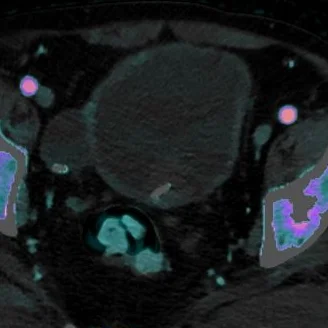

Painless hematuria

Gopal Punjabi

September 4, 2018